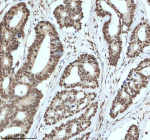

Immunohistochemical staining of IRF2BP1 using anti-IRF2BP1 antibody. IRF2BP1 was detected in a paraffin-embedded section of human colon adenocarcinoma tissue. Heat mediated antigen retrieval was performed in EDTA buffer (pH 8.0, epitope retrieval solution). The tissue section was blocked with 10% goat serum. The tissue section was then incubated with 2 ug/ml rabbit anti-IRF2BP1 antibody overnight at 4oC. Peroxidase Conjugated Goat Anti-rabbit IgG was used as secondary antibody and incubated for 30 minutes at 37oC. The tissue section was developed using an HRP secondary and DAB substrate.